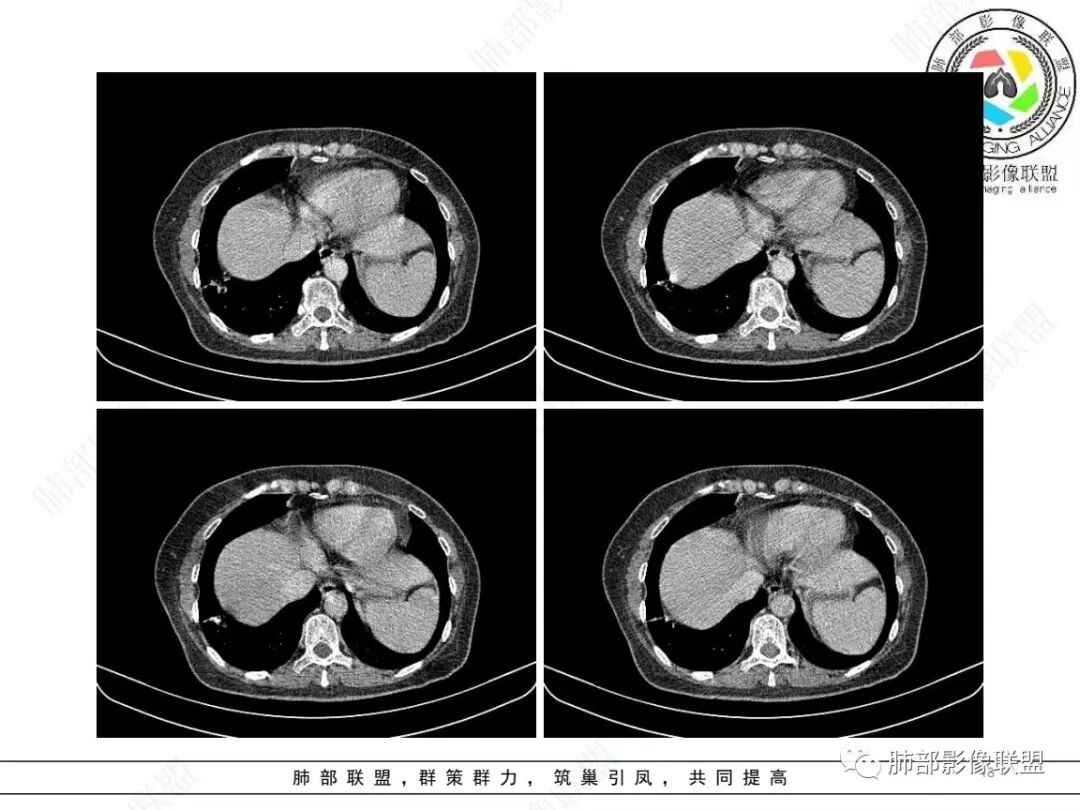

2、影像特点:右肺下叶胸膜下不规则结节,矢状位整体病灶沿着支气管方向呈斑片状,不均匀强化。病灶边缘多平直、凹陷(从部分层面可见极其像月牙铲),缺乏膨隆感,周围可见多发长索条影,病灶内可见多发充气支气管影,大部分支气管完全贯通病灶并轻度扩张,极少支气管进入病灶内堵塞,观察横断位视频、部分层面病灶周围可见边界欠清的ggo。纵隔窗病灶内未见明显钙化影。未见卫星病灶及树芽征。

3、综合分析:中老年女性胸膜下不规则结节,无特殊临床表现,实验室检查亦无特殊,病灶在部分断面呈斑片状,边缘多平直甚至凹陷,缺乏分叶及膨隆感,未见粗短毛刺及胸膜凹陷,部分层面似见”月牙铲“样外形,但缺乏张力的“月牙铲”不太可靠。灶周磨玻璃晕也会让人警惕肺腺癌可能,磨玻璃影边界是否清晰常须薄层仔细分辨。

实性密度为主结节影,支气管密切相关,边缘多平直,缺乏分叶膨隆感,缺乏张力,有磨玻璃晕但边界不清。更符合慢性炎性病变。